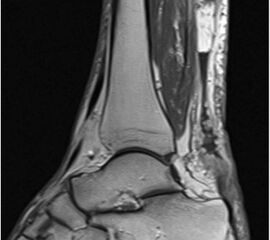

Der geübte Untersucher kann anhand des seitlichen Röntgenbildes die Diagnose einer Achillessehnenruptur stellen. Die Konturen des Kager-Dreiecks – gebildet von der ventralen Begrenzung der Achillessehne, der posterioren Tibiakante und der kranialen Kalkaneuskortikalis – verstreichen im Rupturfall (Kager 1939). Die MRT- Diagnostik spielt für die Primärdiagnostik der frischen Achillessehnenruptur eine untergeordnete Rolle und ist im Normalfall nicht notwendig. Anders verhält es sich bei den chronischen Rupturen. Hier ist die MRT ein wichtiges Diagnostikum insbesondere in Hinblick auf die Beurteilung der Sehnen- und Muskeldegeneration (Abb. 6).

Abbildung 6

Neben der strukturellen Wiederherstellung der Sehne ist die funktionelle Beurteilung des Muskels von entscheidender Bedeutung. Ist es bereits zu einer Degeneration der Muskeln gekommen, kann ein gutes funktionelles Ergebnis, trotz subtiler Sehnenrekonstruktion, nicht erreicht werden. Die Arbeitsgruppe um Hoffmann et al. 13 konnte in ihrer Arbeit zeigen, das es - ähnlich wie bei Patienten mit chronischen Supraspinatusrupturen - zu fettigen Degenerationen und Ödemen der Muskulatur kommt, die im MRT nachweisbar sind. Wir empfehlen die MRT- Untersuchung des gesamten Unterschenkels und nicht nur die rupturnahen Bereiche. Des Weiteren lässt die MRT eine Beurteilung der Degeneration der umliegenden Sehnenanteile zu. Die Computertomographie sollte nur in Ausnahmefällen zum Ausschluss von Begleitverletzungen (Abb. 7) durchgeführt werden und gibt uns sonst keinen weiteren Informationsgewinn.